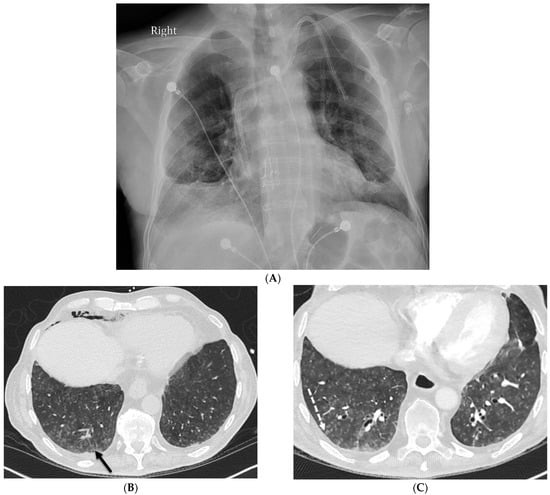

5.2. Kaposi’s Sarcoma

5.3. Lymphoma

| Kaposi’s sarcoma | nodular | + | + | + | − | − | + | − | − | + |